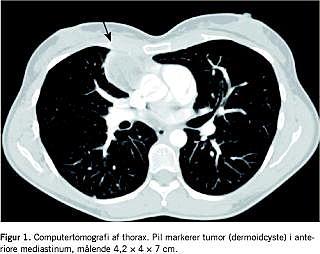

Patienten blev henvist til magnetisk resonans (MR)-skanning af columna cervicalis med henblik på cervikalt rodtryk. MR-undersøgelsen viste kyfose af columna cervicalis samt udtalte diskusdegenerative forandringer på niveau C3/C4, C4/C5 og C5/C6 med tilhørende unkovertebral artrose. Der var ingen tegn på spinalstenose eller rodkanalstenoser. Røntgen af thorax viste en velafgrænset tumorproces på 7,4 × 4 cm beliggende anteriort for højre hilusregion. Efterfølgende computertomografi af thorax og øvre abdomen (Figur 1) viste en delvis fedtholdig, velafgrænset proces i mediastinum anterior - der blev beskrevet som en proces med benigne karakteristika: lipom, dermoidcyste eller et tymom. Supplerende MR-skanning gav ikke yderligere afklaring. Patienten blev henvist til Århus Universitetshospital, hvor man foretog midtlinjesternotomi og efterfølgende fjernede en til perikardiet og højre lunge fast adhærent højresidig mediastinal tumor. Tumor fjernes in toto med et lille lungeresektat og et lille stykke af perikardiet. Det postoperative forløb var ukompliceret. Derefter aftog såvel de respiratoriske symptomer som dem fra overekstremiteterne og efterlod patienten helt symptomfri. Histologisvaret viste mediastinal dermoidcyste og hyperplastisk tymusvæv. Reaktiv pleurafibrose og inflammation. Intet malignt.

Dermoidcyster i mediastinum ses på røntgen af thorax eller computertomografi (CT) oftest som en asymmetrisk masse i anteriore mediastinum. Ved CT ses en afrundet tumor med en velafgrænset kapsel, der består af en eller flere cyster med velafgrænsede vægge. Der kan forekomme forkalkninger. Tumorindholdet har vand- eller fedtdensiteter vurderet på CT. Indhold af rudimentære tænder, ossifikationsfoci eller fedt-væske-spejl er patogonomiske for demoidcyster [4, 5].